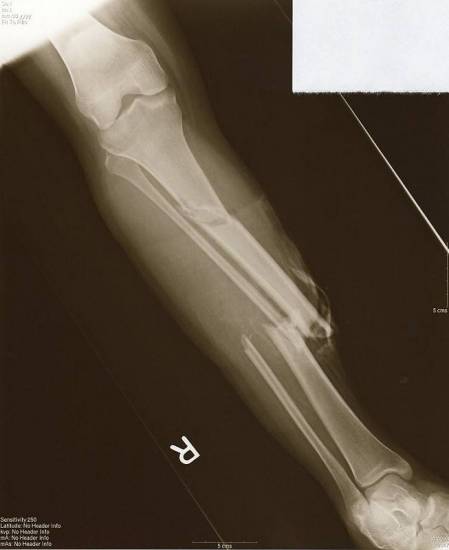

То, как быстро пройдет лечение перелома плюсневых костей стопы, срастется поврежденная кость, и будут ли осложнения, зависит правильность и своевременность оказания первой помощи пострадавшему. Тактика дальнейшего лечения напрямую зависит от тяжести повреждения и от его локализации. Определить локализацию повреждения можно с помощью тщательного осмотра и двухпроэкционного рентгеновского снимка, который покажет место травмы:

- основание плюсневой кости стопы,

- диафиз,

- шейка или головка.

А также линию разлома и наличие/отсутствие смещения.

Общая информация о переломе голени

Перелом голени происходит в результате прямого удара по ней, а также при деформировании конечности с неподвижной стопой. Четверть подобных травм происходит во время дорожно-транспортных происшествий.

Такие травмы бывают множественные и единичные, по типу линии перелома – прямые, косые и в виде спирали; с осколками и без них; открытого и закрытого типа. Также может быть одновременно перелом обеих костей голени и каждой по отдельности, перелом голени со смещением и без.

К главным признакам перелома голени можно отнести болевые ощущения и невозможность перенести опору на поврежденную ногу. При переломе со смещением поврежденная конечность слегка укорачивается, а ее положение в плоскости будет аномальным. Обломки при переломе со смещением могут резко менять свое положение относительно друг друга в вертикальном и горизонтальном направлении.